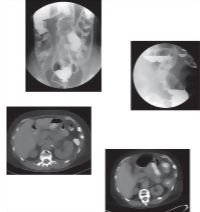

Large Intestine Imaging Studies